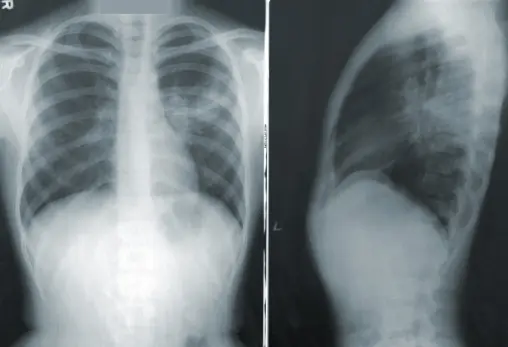

Главный внештатный специалист по пульмонологии Минздрава Самарской области Юлия Богданова перечислила отличительные симптомы пневмонии. Врач напомнила, что пневмония - инфекция дыхательных отделов респираторного тракта, характеризующаяся вовлечением в патологический процесс альвеол, а также бронхов мелкого калибра и бронхиол.

- Развитие очагового воспаления на уровне альвеол принципиально отличает пневмонию от других инфекций со схожими клиническими симптомами, - пояснила Богданова.